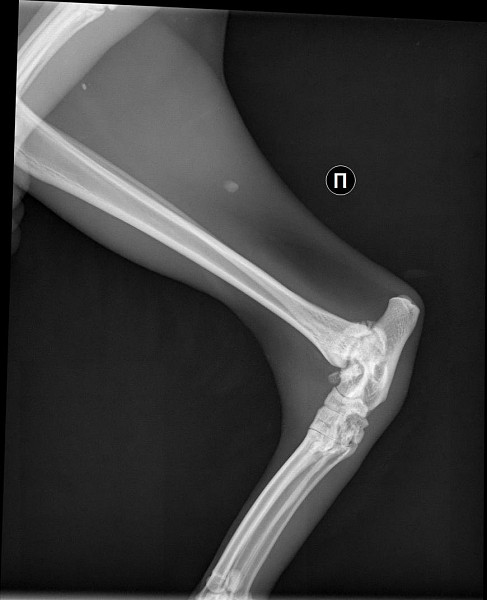

Рентгеновские снимки перелома лапы у кота: диагностика и лечение